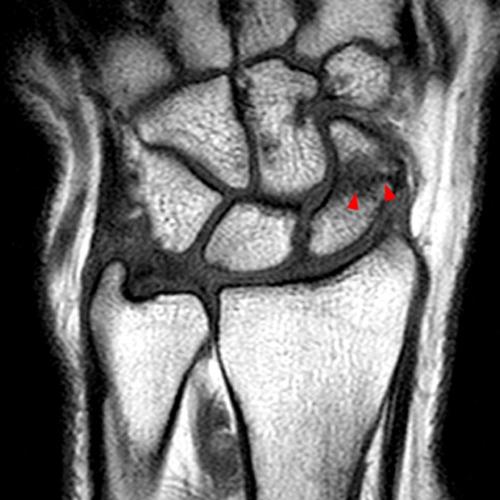

Figure 9: A 33-year-old female with radial-sided wrist pain for the evaluation of de Quervain’s tenosynovitis. Axial fat-suppressed proton density-weighted axial images at the proximal (9A) and mid-portion (9B) of the first extensor compartment demonstrate tenosynovitis with peritendinous fluid signal (arrows), overlying extensor retinacular and soft tissue edema, and marrow edema in the subjacent radius (arrowheads).